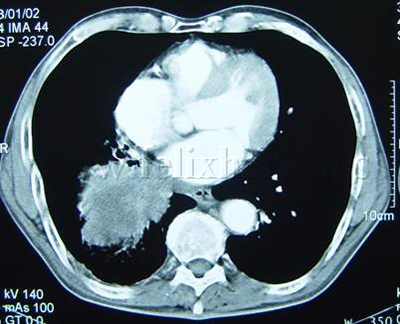

Cáncer de pulmón